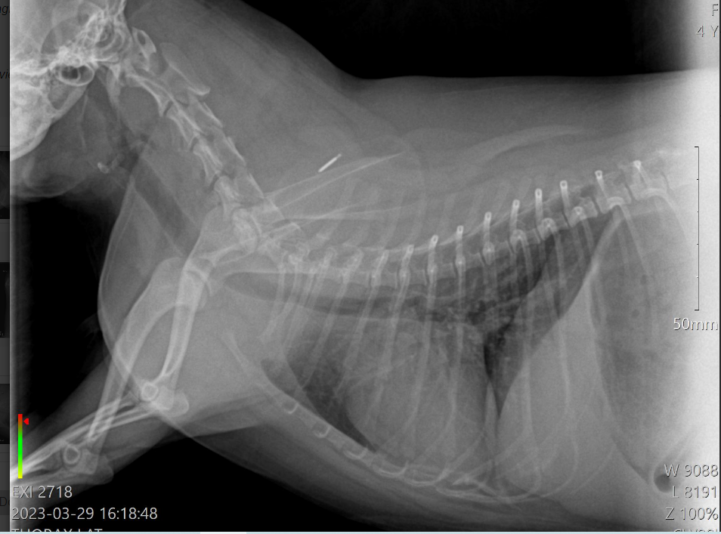

Hello

i am uploading this post about a case of mine.

Its about a 8 year old dog, boomer, castrated, that 2 months ago started to cough (dry cough). Back then, i gave to the dog doxycycline and metacam for 10 days and the problem was completely solved. Now, after 2 months, the problem came back. The dog is coughing only when is getting excited,…